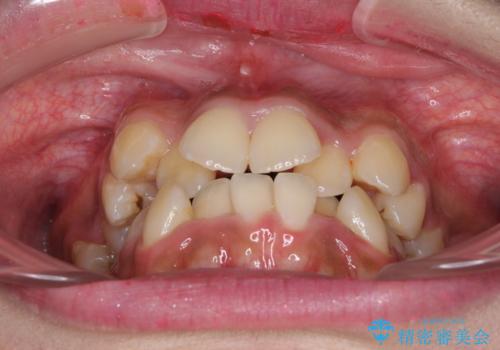

- 八重歯と上下前歯のでこぼこを気にして来院された患者様です。

上下前歯部叢生のスペース獲得のため、上下顎左右小臼歯各1歯(計4本)と全ての親知らずを抜歯して、矯正治療を行うこととしました。